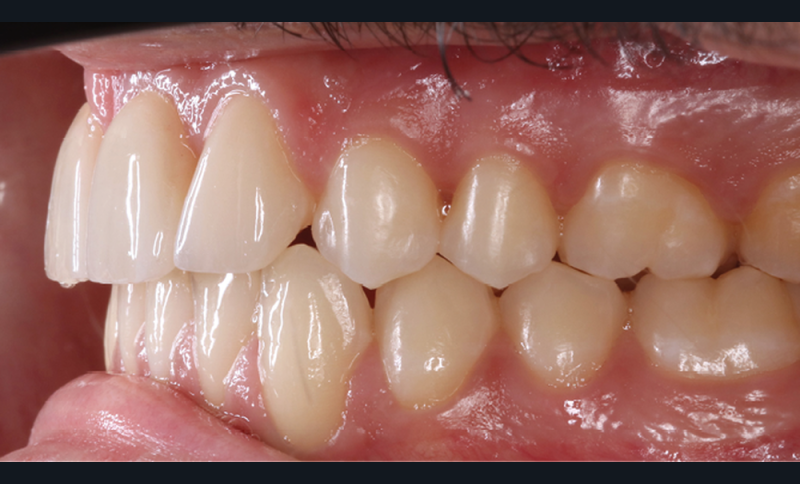

Antony, 11 ans se présente initialement pour une demande esthétique concernant ses deux incisives centrales qu’il trouve trop grosses (fig. 1a-c).

Le profil est convexe et associé à une inocclusion labiale au repos. Il s’agit d’une classe II squelettique sur un schéma facial normodivergent. Les rapports occlusaux sont de classe II bilatérale (complète au niveau molaire) avec des incisives inférieures vestibulo-versées. La 21 est géminée et la 11 vraisemblablement fusionnée avec un germe surnuméraire, sans altération de la formule dentaire. Du fait du diamètre mésiodistal fortement augmenté des incisives centrales, et du manque de place à l’arcade maxillaire qui en découle, les 12 et 22 sont en inversé d’occlusion en palato position. Les 53 et 63 sont persistantes sur l’arcade avec une inclusion en transposition incomplète de la 13, dont la cuspide se situe entre la racine de la 12 et celle de la 11 résorbée (fig. 1d-g).